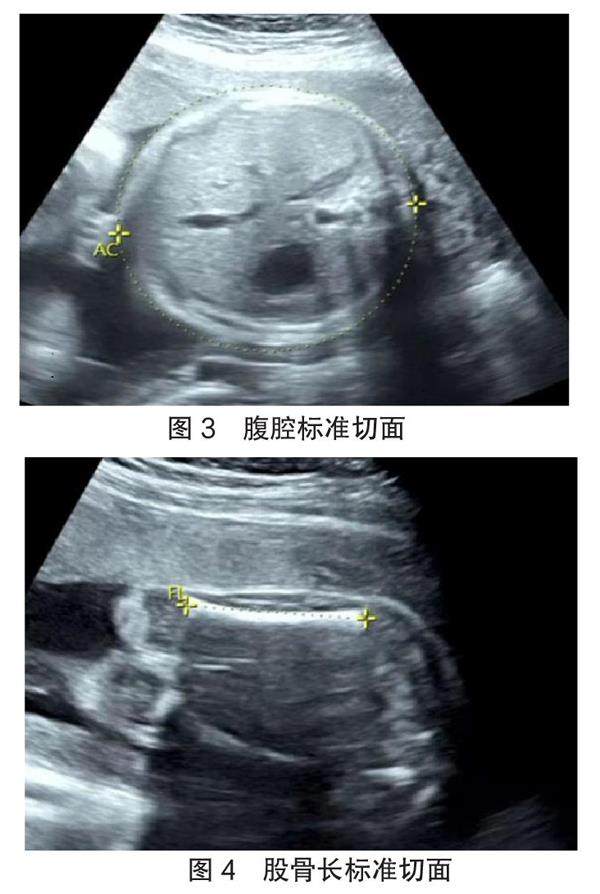

【摘要】 目的 根据胎儿各超声测量值,应用线性回归构建方程预测胎儿出生体质量,并分析各超声测量参数与胎儿出生体质量的相关性。方法 回顾性收集159名新生儿出生体质量及分娩前3 d内胎儿双顶径(biparietal diameter,BPD)、头围(head circumference,HC)、腹围(abdominal circumference,AC)、股骨长(femur length,FL)测量数据,使用SPSS 26.0统计学软件依据胎儿超声测量值和胎儿实际超声体质量推导出预测体质量公式,应用线性方程公式计算各胎儿出生体质量预测值,分析对比各胎儿体质量实际值与预测值,分析BPD、HC、AC、FL与胎儿出生体质量的相关性。(剩余6886字)